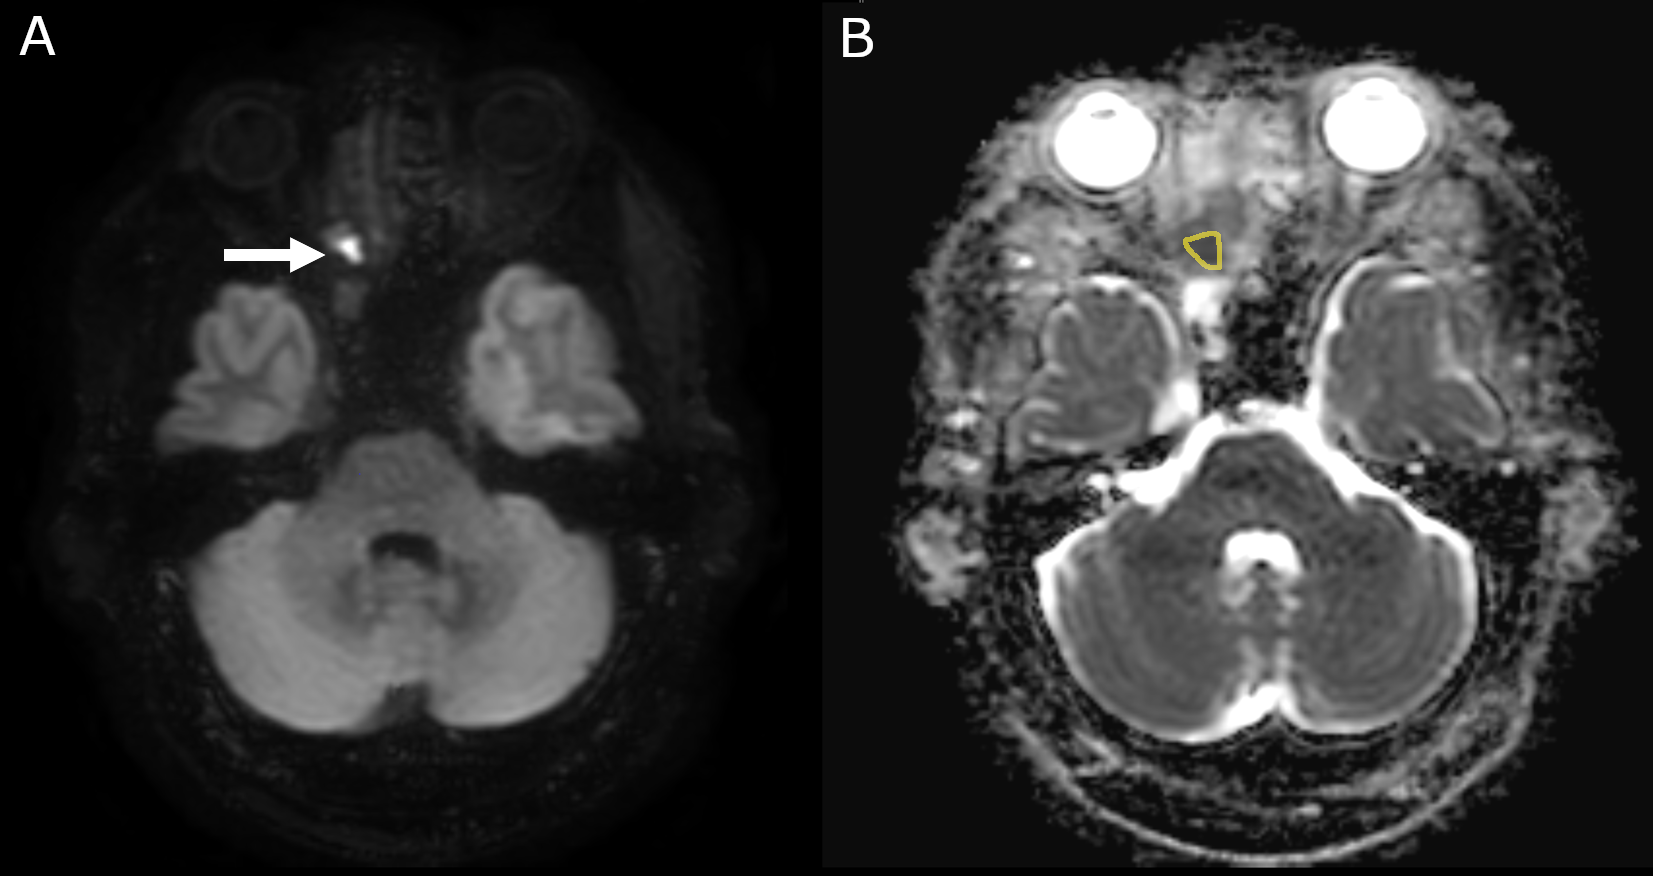

While some patients with recurrent nasopharyngeal carcinoma show response or stable disease to systemic treatment, many patients will have progressive disease, which is invariably lethal [13, 19]. Nevertheless, futile treatments should be avoided due to associated toxicity [13, 9]. To suspend futile treatment as soon as possible an imaging biomarker is desirable which accurately classifies treatment response earlier than change in morphologic lesion size, the current standard. A promising biomarker in this context is diffusion weighted magnetic resonance imaging (DWI) [18]. DWI depends on the differences in the movement of water molecules based on Brownian motion, which can be quantified by the apparent diffusion coefficient (ADC). An exemplary measurement of ADC is shown in Figure 3. Change in ADC has shown promise as an early treatment response marker in various tumors, including nasopharyngeal carcinoma [18, 28, 29, 30].